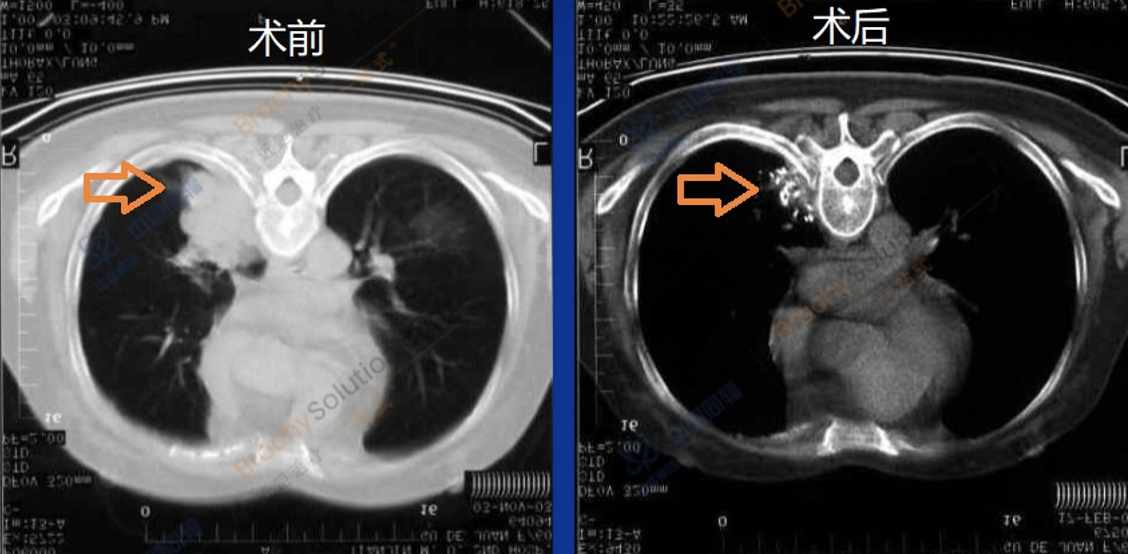

碘粒子植入后即刻开始发挥作用,大部分患者在术后3到7天内可感到疼痛缓解,术后2到3个月时,肿瘤体积变化最快,缩小最明显,之后可以持续性缩小。